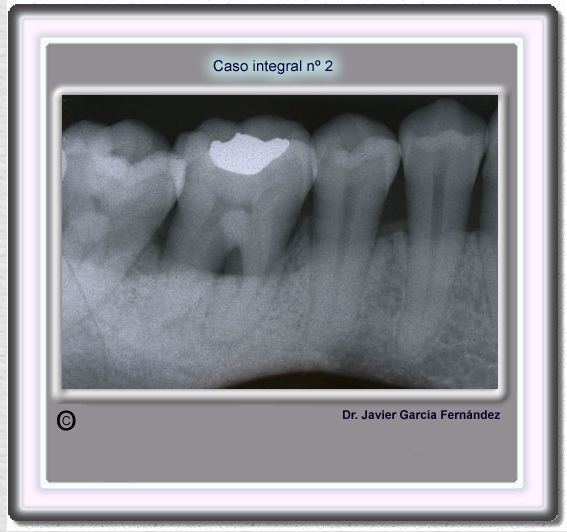

image 19